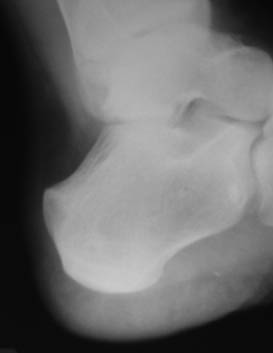

Уважаемый Николай Александрович Корышков, спасибо за проявленное

внимание к  случаю. Выкладываю снимки и томограммы левой пятки и

контрлатеральную, здоровую. Пациенту 19 лет, беспокоят ноющие боли.

Лечили блокадами и физиопроцедурами.